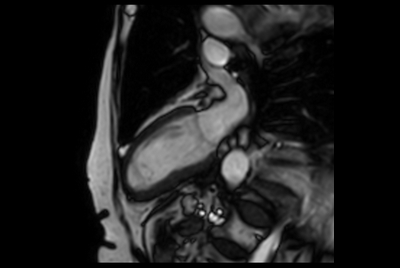

Acute myocardial infarction